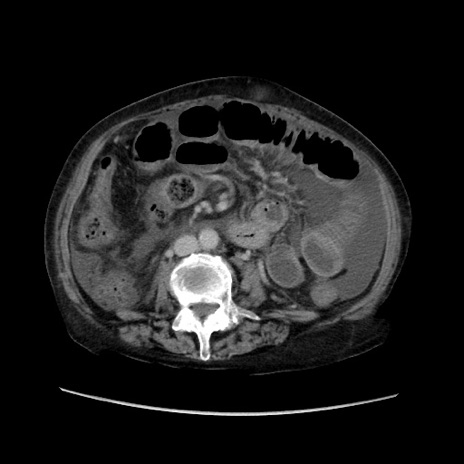

症例31(横断像)

【症例】80歳代 女性

【主訴】腹部膨満感

【現病歴】他院にて肝硬変にてフォロー中。1週間前から便秘、腹部膨満感、臍部腫瘤あり受診となる。

【既往歴】肝硬変

【身体所見】腹部膨隆あり、皮膚変化なし、疼痛なし。

【データ】WBC 4600、CRP 0.25